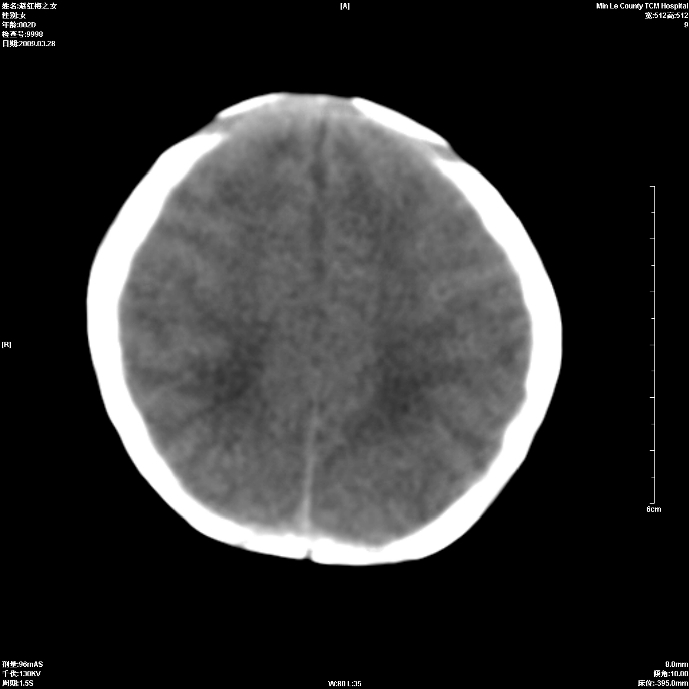

标题: PED1815:患儿出生两天,哭闹不安,囟门饱满 [打印本页]

标题: PED1815:患儿出生两天,哭闹不安,囟门饱满

少量蛛网膜下腔出血,有窒息史吗?

支持考虑新生儿缺血缺氧性脑病伴蛛网膜下腔出血,请结合临床,建议随访复查

缺血缺氧性脑病伴蛛网膜下腔出血.

支持缺血缺氧性脑病伴少量蛛网膜下腔出血。

支持 1)缺氧缺血性脑病。2)蛛网膜下腔出血。

z新生儿缺血缺氧性脑病,蛛网膜下腔出血!

若有窒息史,考虑缺血缺氧性脑病伴少量蛛网膜下腔出血。